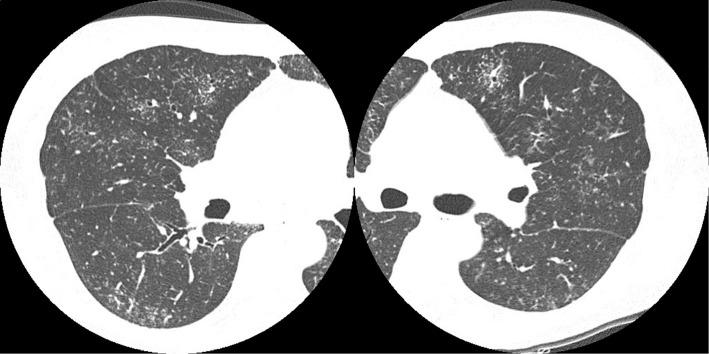

Katano Takuma, Hagiwara Eri, Ikeda Satoshi, Ogura Takashi

Department of Respiratory Medicine, Kanagawa Cardiovascular and Respiratory Center, Japan.

Intern Med. 2019 Feb 15;58(4):617-618. doi: 10.2169/internalmedicine.1281-18. Epub 2018 Oct 17.